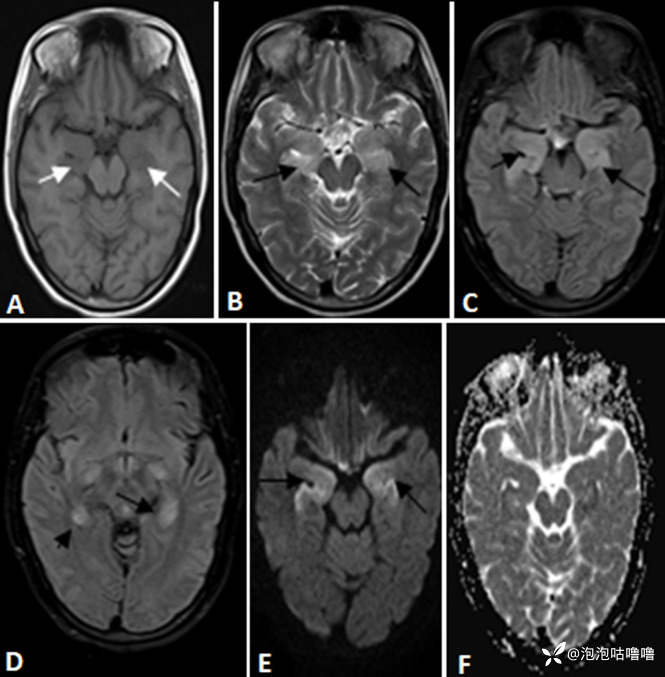

大脑磁共振成像显示 T1 加权图像上双侧内侧颞叶低信号(图 A 标有白色箭头); T2 加权双侧内侧颞区高信号(图 B); FLAIR序列(图C和D用黑色箭头标记),无扩散限制; (图E,扩散加权图像和F,表观扩散系数图像)

诊断评估:血液检查显示阴离子间隙正常、代谢性酸中毒、低钾血症、钠水平正常。血清钾水平为 2.7mmol/L,给予静脉内纠正和口服补钾。血常规、肾功能和甲状腺功能检查、钙、镁、病毒标志物和抗甲状腺过氧化物酶抗体均在正常范围内。红细胞沉降率 (ESR) 为 43 毫米/小时,连续检测显示轻度血小板减少症。因患者认知能力不断恶化,给予头颅CT检查,结果显示正常。动脉血气显示高氯性代谢性酸中毒,阴离子间隙(AG)正常。血清皮质醇和醛固酮水平正常。总体情况提示远端肾小管酸中毒(RTA),腹部超声检查显示多尿和肾脏高回声,给予对症治疗。后进一步给予头颅MRI检查,结果显示 T2 和 FLAIR 高信号涉及两个内侧颞叶,没有任何扩散限制,并且有最小的对比增强提示边缘脑炎(图1)。随后,她出现间歇性局灶性癫痫发作,主要涉及面部,伴有眼睑、嘴唇和右上肢抽搐。脑电图显示偶尔出现左颞尖峰。然而,在癫痫发作期间,她有定向力和服从性,没有局灶性缺陷,因此排除了癫痫持续状态。脑脊液 (CSF) 研究显示淋巴细胞增多,有 20 个细胞(P5、L95),无糖过多和蛋白质轻度升高(62mg/dl)。脑膜脑炎脑脊液 (CSF) 聚合酶链反应 (PCR) 检测结果显示细菌和病毒呈阴性。她的血液和脑脊液培养物是无菌的。脑脊液和血清的自身免疫病因包括 NMDA-R 抗体、LGI1、CASPr2、GAD-65、GABABR、Anti Hu、Ri、Ma-2 均为阴性。